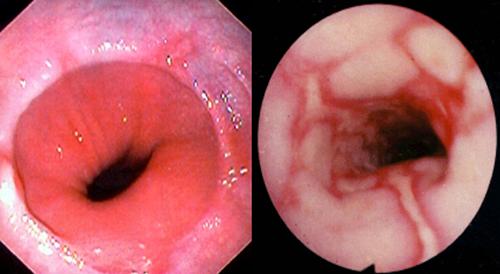

Los métodos de diagnóstico van desde la endoscopía digestiva alta hasta las radiografías, principalmente para ver el nivel de daño en las paredes esofágicas y estomacales, y ahí evaluar de qué carácter es la patología en específico porque “eso definirá si es que el tratamiento será médico o quirúrgico”, indica el médico.

Uno de los niveles de daño más comunes es la esofagitis, inflamación de las paredes esofágicas, pero también puede derivar en algo más grave como el llamado Esófago de Barrett, donde existe un reemplazo de la mucosa normal del epitelio esofágico por epitelio intestinal, habiendo un cambio anormal de las células de la porción terminal del esófago, es decir, una metaplasia. "Por eso es importante la fase de diagnóstico, y el tratamiento dependerá mucho del paciente también. Por ejemplo, en pacientes más jóvenes se recomienda de inmediato la cirugía, pero en un primer momento el tratamiento siempre es médico, junto con un cambio en la dieta y los hábitos alimentarios", comenta el Dr. Braghetto, quien dice que en materia de dieta se indica que se evite el alcohol, el café, los aliños, los picantes, las bebidas gaseosas, la cerveza, la cebolla cruda, las frituras, cremas, salsa de tomate, o sea "no se coma un choripán con pebre, por favor, si sospecha de esta condición", indica el especialista.